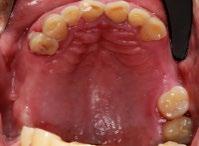

• Estudios radiográficos (ortopantomografía):

Se observa el órgano dentario 33 retenido de manera transversal con un botón de ortodoncia colocado como alternativa durante el anterior tratamiento (Figura 2).